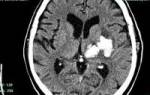

• Бесконтрастная компьютерная томография (КТ) — надежный метод диагностики острых гематом головного мозга. КТ позволяет выявить гематому, её объём и влияние на структуры головного мозга. На основании КТ-снимков нейрохирург определяет тактику и объём операции. Большинство стационаров, особенно экстренной помощи, оснащены КТ-аппаратами. Однако в хронической стадии и при сосудистых пороках без кровоизлияния КТ может не дать необходимой информации. В таких случаях используют МРТ.

В диагностике клинической значимости нейровизуализация играет ключевую роль. Первоначально для исследования головного мозга назначают компьютерную томографию (КТ). Этот недорогой метод позволяет быстро определить наличие крови в веществе головного мозга, а также расположение и объем сгустка. Информативность КТ максимальна через 2-3 недели после появления гематомы (максимум 5 недель). В этот период участок внутримозговой гематомы (ВМГ) имеет повышенную плотность, что облегчает диагностику, и можно ограничиться одной КТ.

С течением времени (в среднем через 14-21 день) плотность геморрагической массы уменьшается, и она становится изоплотной, то есть приближается к нормальным мозговым тканям. В этот период и позже качественные данные о внутримозговой гематоме и состоянии мозга предоставляет магнитно-резонансная томография (МРТ).